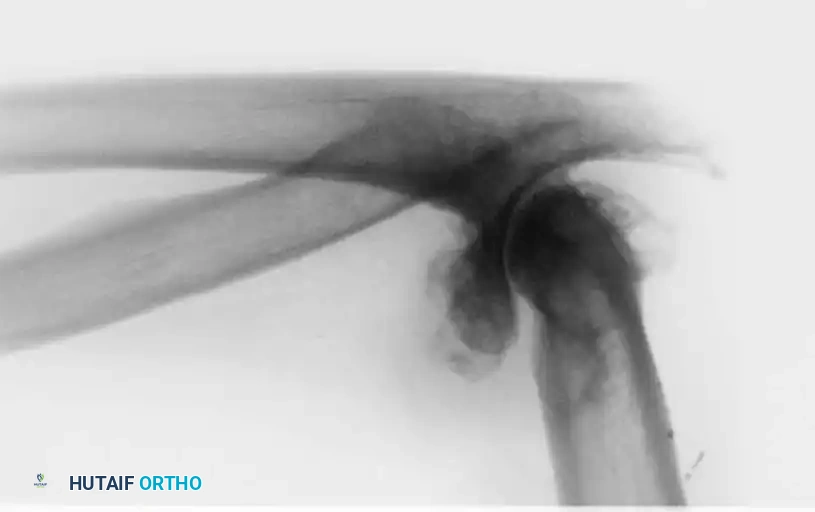

Associated Surgical & Radiographic Imaging